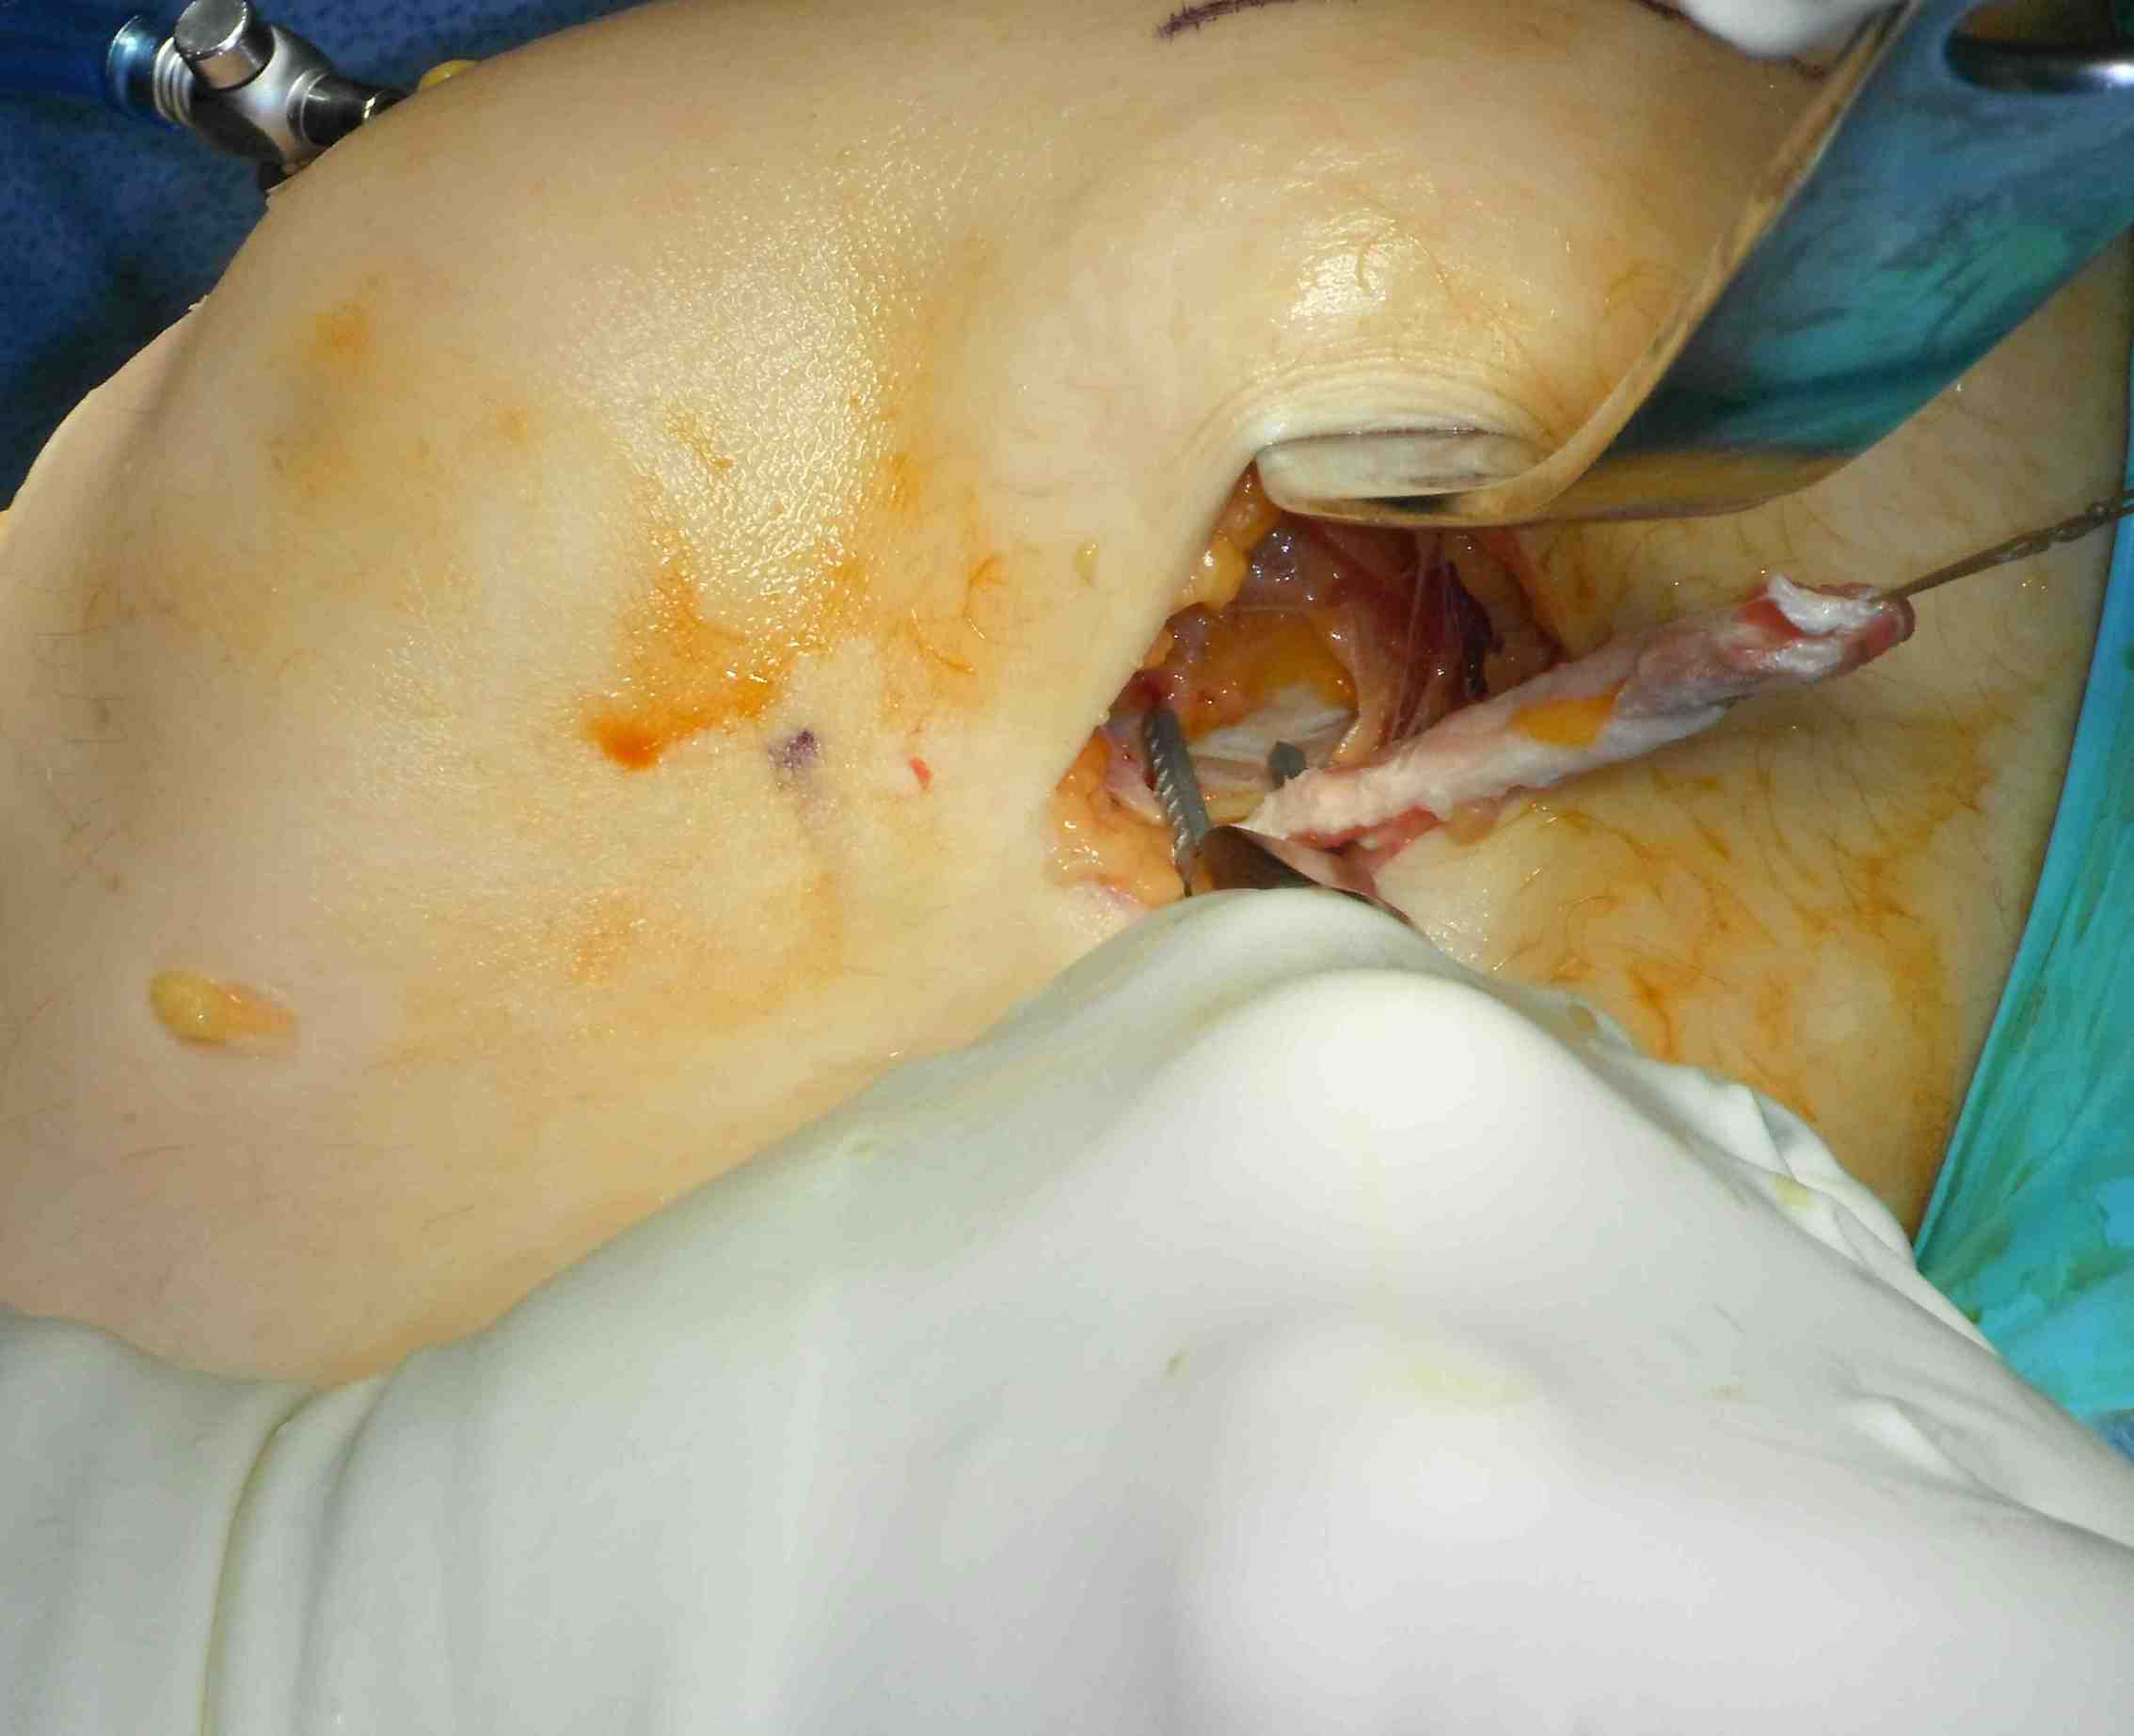

Lateral incision

- divide ITB at posterior aspect of femoral condyle

Pass curved hemostat

- from inside knee via medial arthrotomy

- pass around femoral condyle

- pass suture, retrieve graft